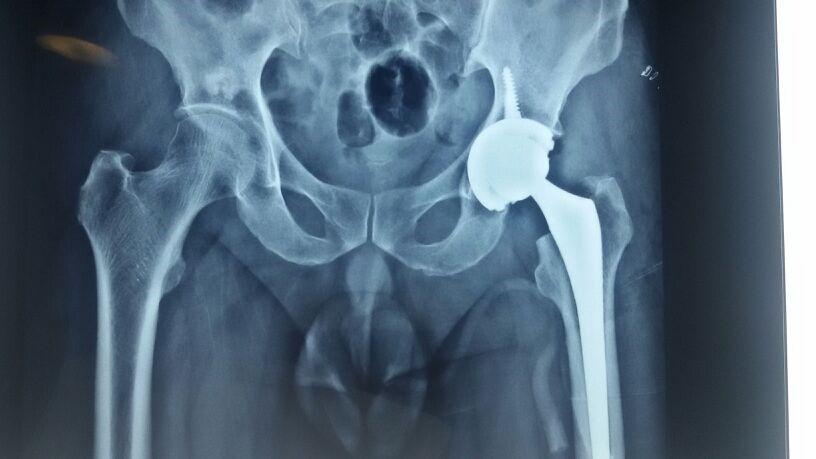

Hip replacement is a surgical procedure in which the hip joint is replaced by a prosthetic implant, that is, a hip prosthesis. Hip replacement surgery can be performed as a total replacement or a hemi replacement.

1. Total Hip Replacement

1. The surgeon removes the painful hip joint and replaces it with an artificial joint.

2. The doctor makes a cut along the side of the hip and moves the muscles connected to the top of the thighbone to expose the hip joint.

3. The ball portion of the joint is removed and an artificial joint is attached to the thighbone using either bone cement or by press-fitting an uncemented component. The cup side bone is exposed, removing any damaged cartilage, and a new socket is attached to the hip bone either using bone cement or by press-fitting the cup.

4. The new ball part of the thighbone is then reduced into the socket part of the hip. The bearing surfaces are made of metal, ceramic or polyethylene and its combinations.

5.The new joint articulation is between this artificial ball and socket with the least friction and almost no pain.